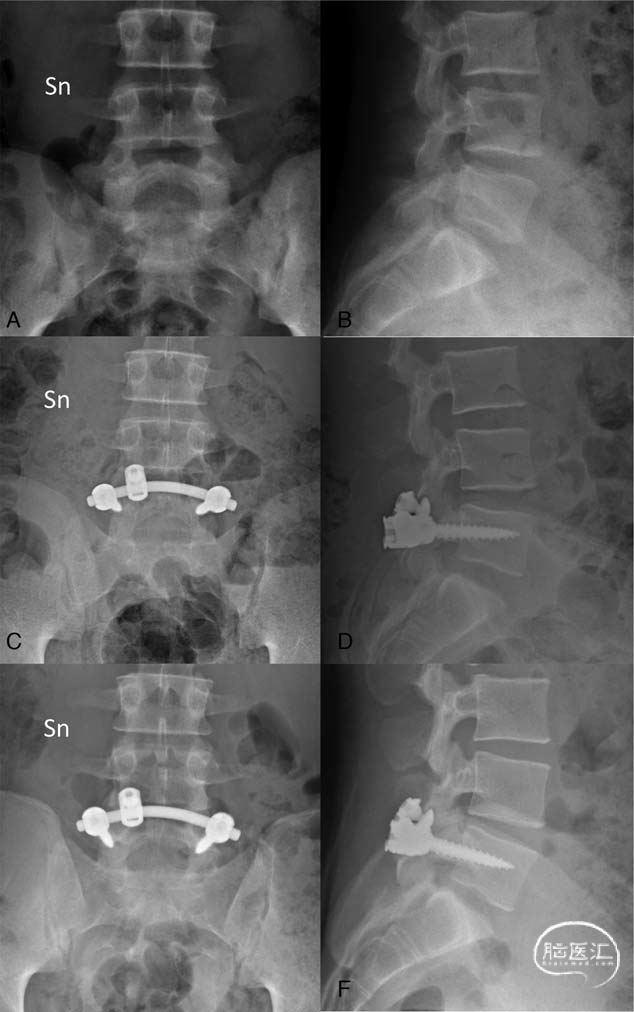

一种新的峡部裂复合修复技术